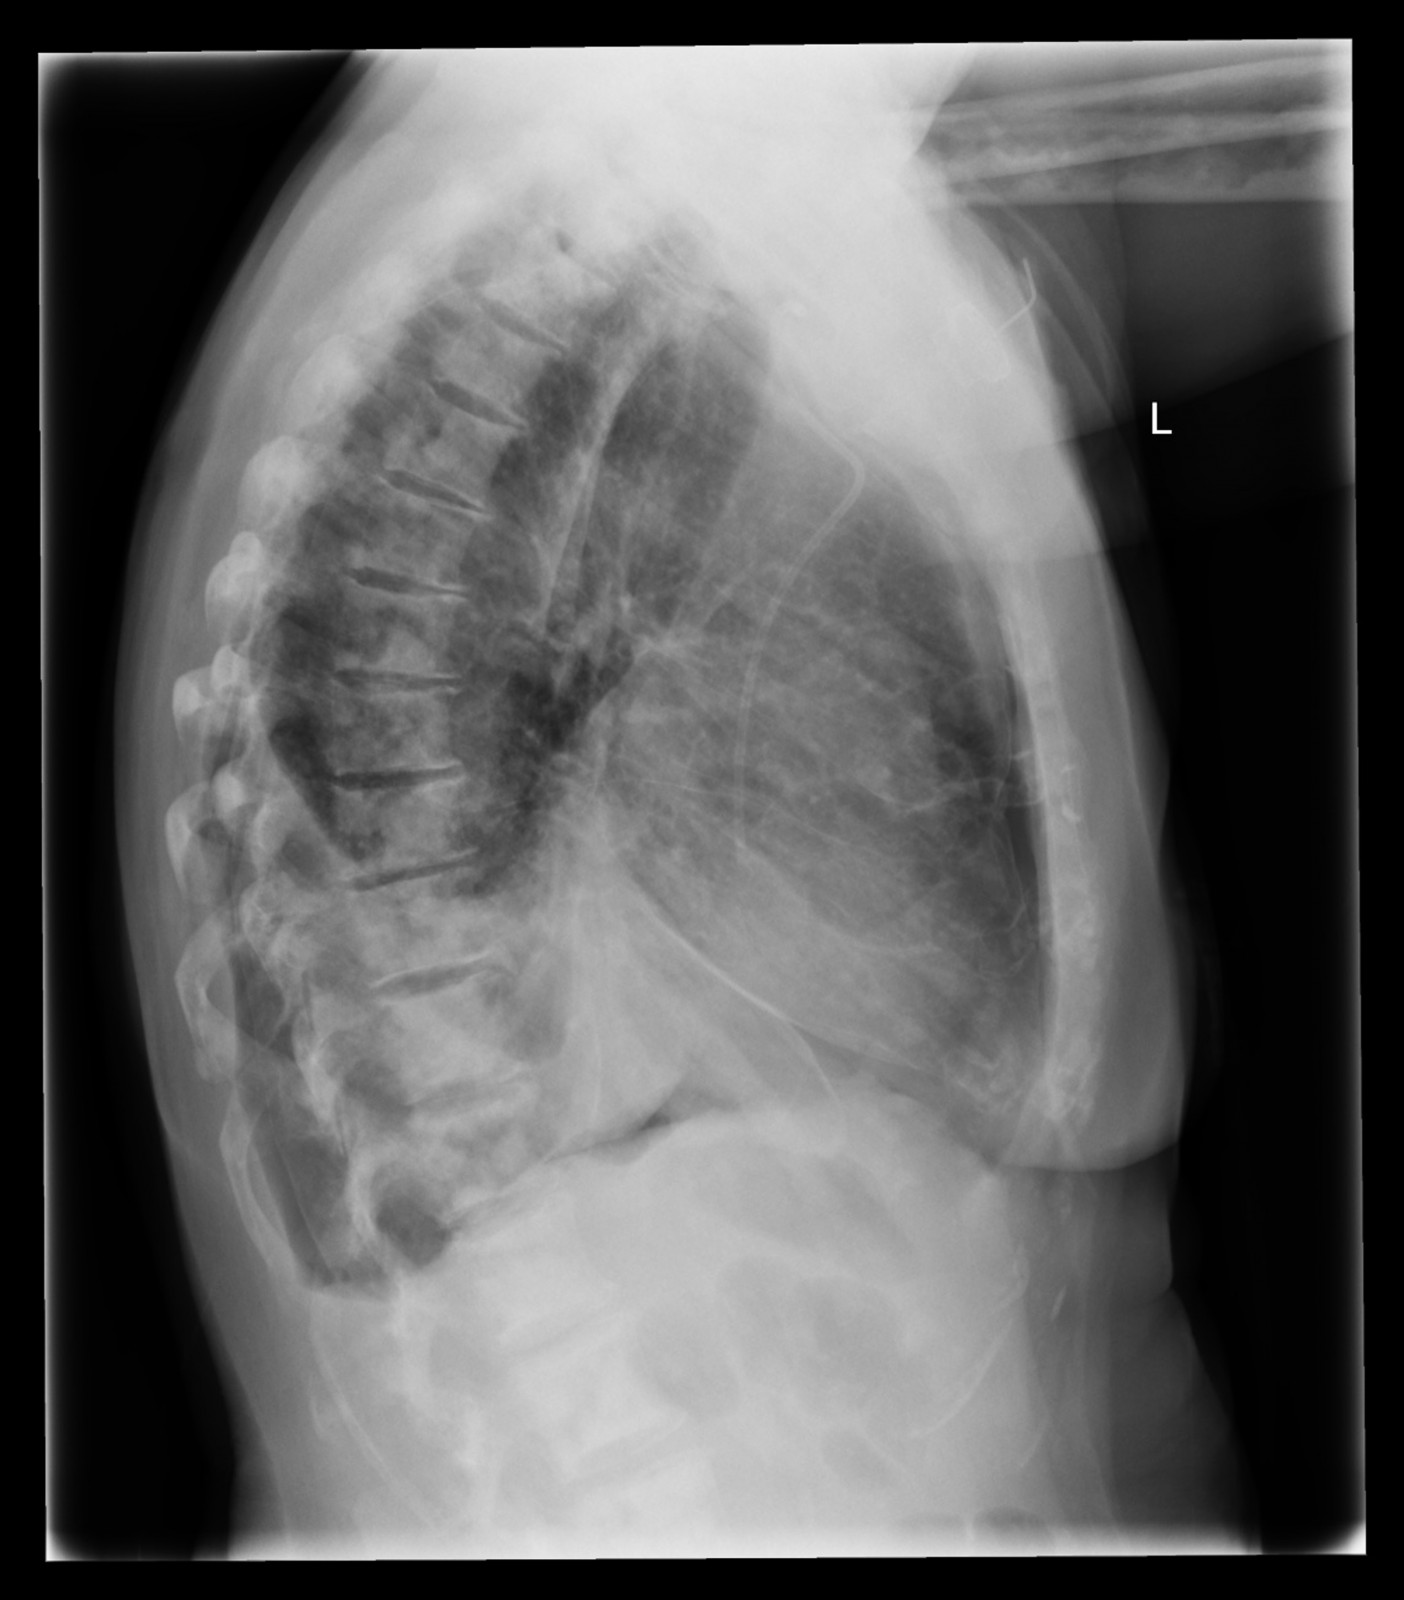

Röntgenfall des Monats Mai 2017 mit Auflösung

74 jährige Patientin mit diffusen Skelettschmerzen und akut aufgetretener Dyspnoe. Z.n. Mammakarzinom rechts.

ap

Bild vergrössern

seitlich